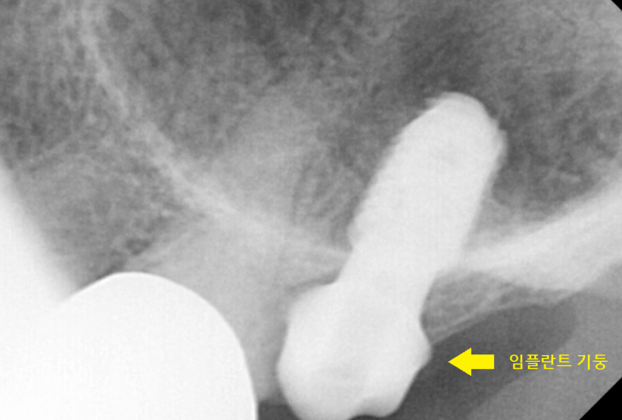

ct 영상을 쥐잡듯이... 돌려보다가

발견했습니다.

ct에서는 치아 내부까지 볼 수 있거든요~

230807

치아를 본드로 붙일 수 있다면 좋겠지만..

아직까지는 개발되지 않았습니다.

어금니 뿌리 쪼개짐 경우에는 뽑아야 통증이 끝납니다.

씹으면서 쪼개진 부분이 계속 벌어져

욱신 욱신하고 우리하고

반복됩니다.